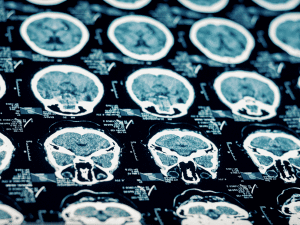

The brain requires a constant flow of oxygen to function normally. A hypoxic-anoxic brain injury can occur when the flow of oxygen to the brain is disturbed, basically starving the brain of the fuel it needs to function. A “hypoxic” event refers to one that causes a partial lack of oxygen to the brain. An “anoxic” event refers to one that causes a total lack of oxygen to the brain. Generally, the more complete the oxygen deprivation, the greater the potential for severe injury to the brain.

Diminished oxygen supply to the brain can cause serious impairments in cognitive skills, as well as in physical, psychological, and other functions. Recovery after a hypoxic-anoxic event can occur, but it depends largely on the areas of the brain affected, and its pace and extent are unpredictable.

A hypoxic-anoxic brain injury can have a catastrophic impact on the lives of those affected. Treatment for this injury can be extensive and costly. Many brain injury victims require extensive rehabilitation and even long term attendant care.